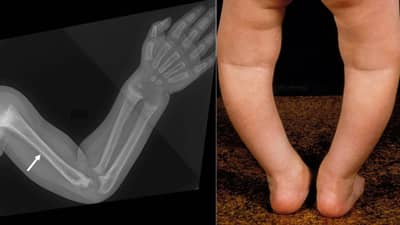

जर विटामीन डी योग्य प्रमाणात मिळालं नाही, तर हाडं कमजोर होऊन नरमही होऊन जातात कारण विटामीन डीच्या कमतरतेमुळे हाडांना कॅल्शियम आणि फॉसफेटचा उणीव जाणवते. काहीवेळानंतर हाडं वेडीवाकडी होतात, ज्याला रिकेट्स असं म्हणतात. सहा महिन्यांपासून चार वर्षांपर्यंतच्या मुलांमध्ये रिकेट्सचा त्रास दिसून येतो.

रिकेट्स नेमका आपल्या मुलांना झाला आहे की नाही, हे ओळखण्याचे काही सोपे पर्याय आहे. त्यातील तीन पर्याय हेही फार महत्त्वाचे आहेत. 1. ज्या मुलांना चालणं, धावणं, उभं राहणं या गोष्ट करणं नीट जमत नाही, त्यांच्यामध्ये रिकेट्स झालेला असण्याचा धोका असतो. 2. ज्या चिमुकल्यांच्या हाडांमध्ये किंवा जिथं हाडं जोडली जातात तिथं सूज असणं, हे देखील एक रिकेट्सचं महत्त्वाचं लक्षण आहे. 3. मनगटात किंवा गुडख्यात सूज असणं, हे रिकेट्सचं प्रमुख लक्षण मानलं जातं. त्याचप्रमाणे जर मुलांमध्ये दात नीट किंवा नैसर्गिकपणे येत नसतील, तरिही ते रिकेट्सचं किंवा विटामीन डीच्या कमतरतेचं लक्षण समजलं जातं.